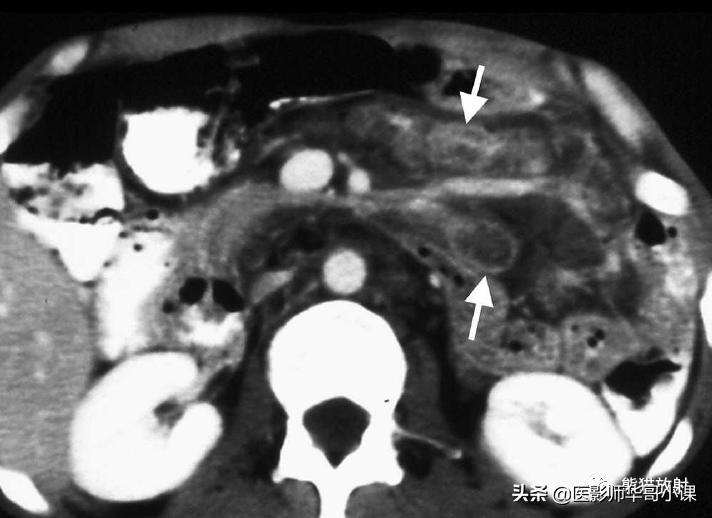

常见的表现 包括游离性或包裹性腹水,肠系膜血管束增粗,腹膜光滑均匀增厚和网膜被小而边界不清的软组织浸润(图)。CT上高CT值的腹水(20~45HU)反映了高蛋白质含量。

淋巴结病变 是腹部结核的常见表现,肠系膜淋巴结常受累。CT上可呈中心低密度伴边缘强化,与组织学上边缘富血管炎性反应围绕中心液化或干酪样坏死相符。这些表现可以提示结核,但不具有特异性,因为低密度的肠系膜淋巴结也可见于惠普尔病、坏死性转移、鸟细胞内分枝杆菌感染,腹腔疾病中的空化肠系膜淋巴结综合征,偶尔也见于淋巴瘤。

腹膜结核。CT显示明显增厚强化的壁层腹膜(黑箭)。注意高密度腹水(光标)